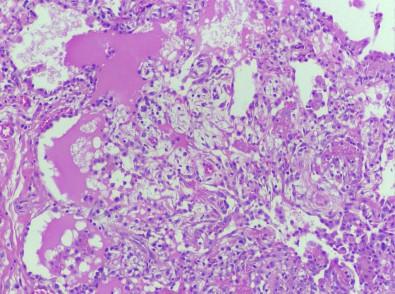

image: Lung tissue from patient with GATA2 deficiency, displaying pulmonary alveolar proteinosis and inflammatory lymphoplasmacytic infiltrate